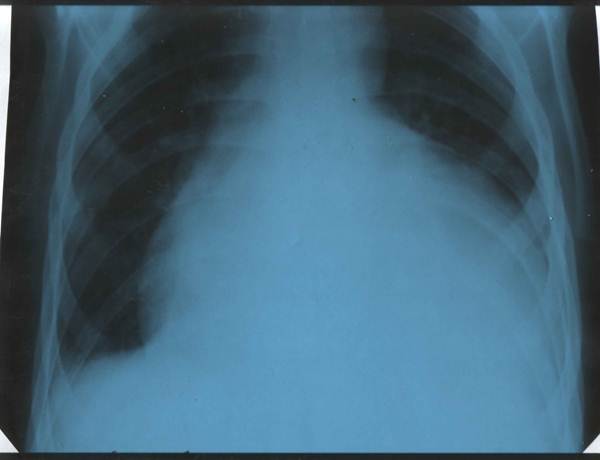

Хлопчик 10 років. Скарги на підвищення температури тіла, в'ялість, дворазову блювоту, підвищену пітливість, появу набряків на нижніх кінцівках. Два тижні тому прооперований з приводу вродженої вади серця, в задовільному стані виписаний додому. Об¢єктивно: відставання в фізичному розвитку, блідість із ціанотичним відтінком шкірних покривів, пітливість, деформація пальців рук та ніг у вигляді "барабанних паличок" та нігтів у вигляді "годинникових скелець". Температура тіла 37,8°С, пульс 140 на хв, дихання 24 на хв, артеріальний тиск 80/40 мм рт.ст. На грудній клітці свіжий рубець після операції на серці. Межі серця різко розширені, права на 1,5 см назовні від парастернальпої лінії, ліва доходить до середньо-підпахвинної лінії. При натискуванні фонендоскопом вислуховується ніжний шум тертя перикарду на фоні послабленої гучності серцевих тонів. Над легенями провідні хрипи, більше в паравертебральній ділянці. Печінка на 4-5 см виступає з під реберної дуги. На нижніх кінцівках відмічається пастозність. ЕКГ,  ЕхоКГ та рентгенограма додається.

ЕхоКГ та рентгенограма додається.

1. Попередній діагноз. Назвати основні симптоми захворювання.

2. Лікувальна тактика.

3. Надати невідкладну допомогу.